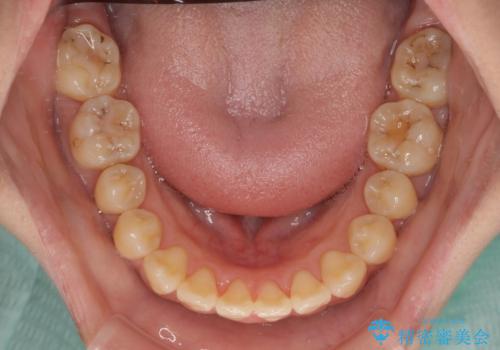

舌の突出癖による開咬と前歯の突出 インビザライン矯正治療

- 上下前歯の非接触と叢生を気にして来院された患者様です。

開咬の改善はインビザラインの最も得意とするところであるため、インビザラインを用いて矯正治療を行うこととしました。